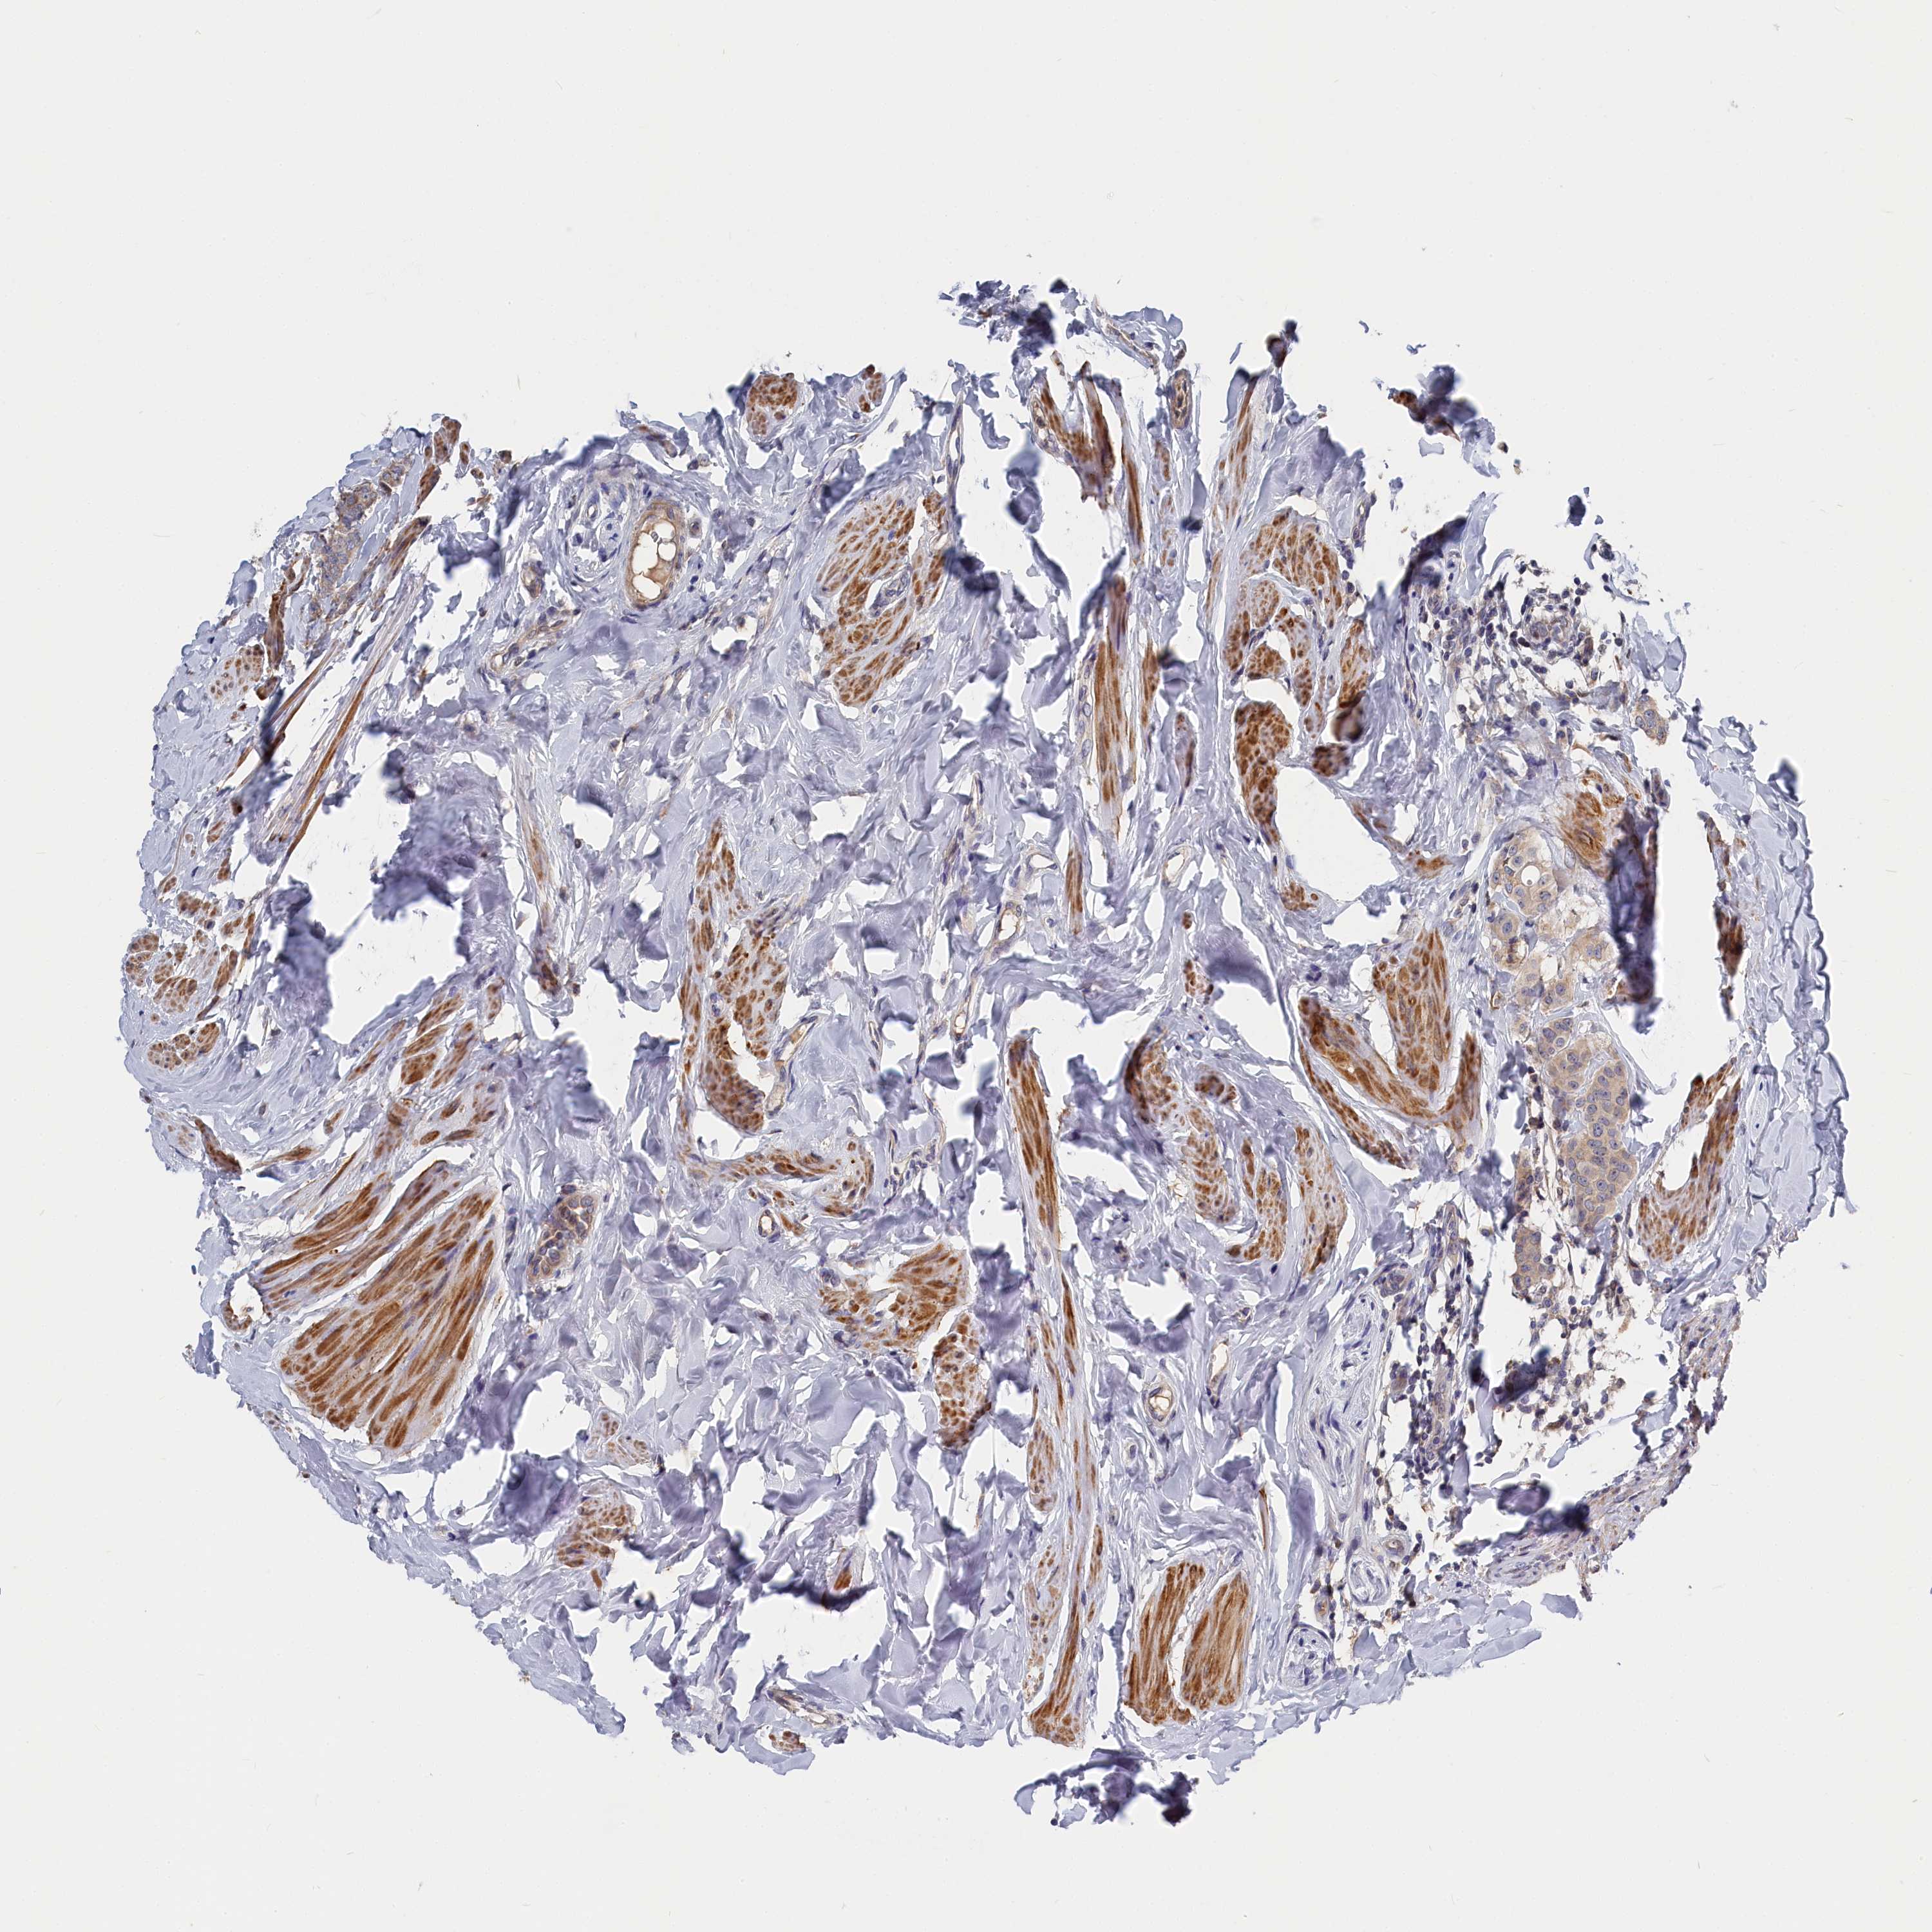

CANCER BREAST CANCER Show tissue menu

BRCA TCGA BRCA VALIDATION PROTEIN EXPRESSION